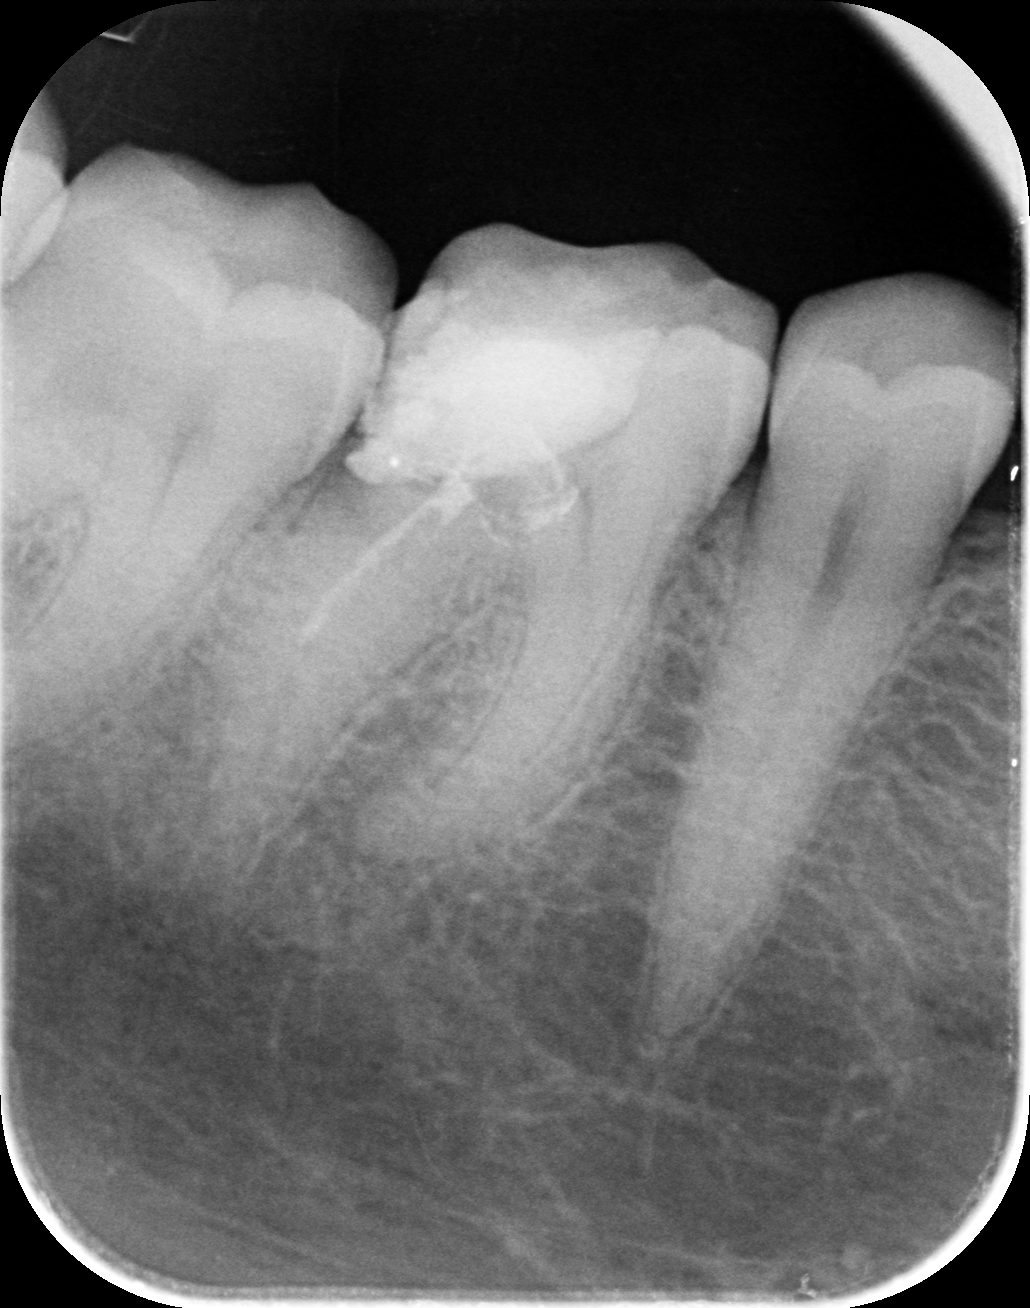

Dantų kanalų gydymas